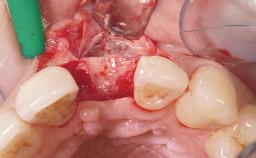

A 30-year-old female patient was referred to the office for the treatment of tooth 11. Her chief concern at the initial visit was to inquire, “Why is my tooth pink?” Upon clinical examination, it was determined that tooth 11 had a previous history of trauma and that the clinical crown had become noticeably pink in color as a result of internal resorption. This diagnosis was confirmed radiographically, indicating a large radiolucency involving the central and distal portions of the clinical crown. It was determined that restoration of this tooth was not possible, and that extraction was indicated. The presence of a mid-line diastema, which the patient wanted to reproduce, directed the treatment plan for tooth replacement utilizing a dental implant.

Bone Augmentation Horizontal|Simultaneous

Augmentation Materials Autogenous chips|Membrane

Guided Surgery No

Soft Tissue Grafting None